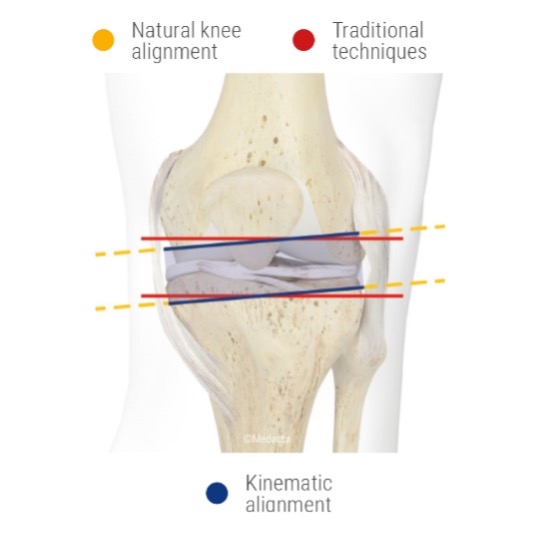

Vereinfachte Darstellung des kinematic Alignement (Fa. Medacta). Das kinematic Alignement folgt der patientenspezifischen Anatomie.

Im Gegensatz zum konventionellen Alignment, das oft auf standardisierten anatomischen Referenzpunkten basiert, versucht das kinematische Alignment, sich an die natürliche Gelenkachse und Bewegung des Patienten anzunähern. Dies kann zu einem individuelleren und oft (aber nicht immer) besseren Ergebnis führen.